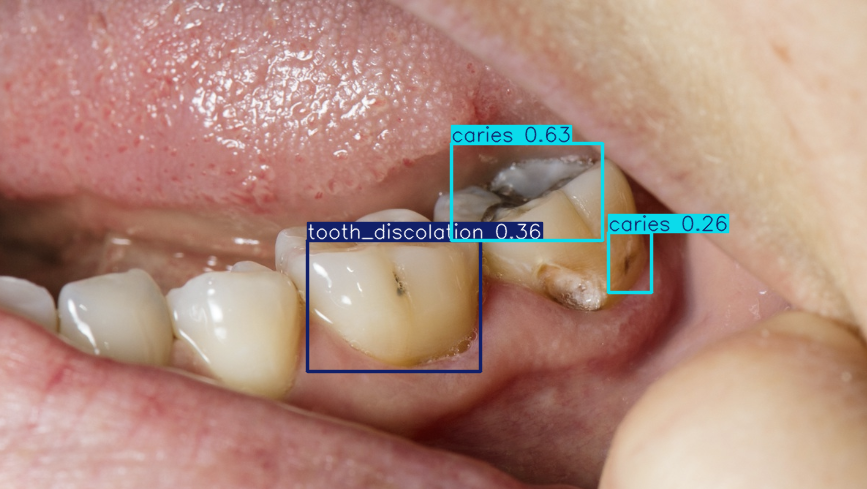

We trained a Computer Vision model on 10,000+ human-labeled dental images from Roboflow using Amazon SageMaker Studio. Our model classifies oral diseases such as ulcers, hypodontia, gum inflammation, caries, calculus, and tooth discoloration.

Successfully trained a Computer Vision AI model capable of detecting oral diseases such as cavities, gingivitis, and tooth discoloration from image data. Built a functional interface for patients to upload photos and receive clear, visualized results, making AI-powered diagnostics more accessible. Managed to create a pipeline that connects AI, cloud tools, and authentication systems — even if not fully deployed, the architecture is in place for future completion.